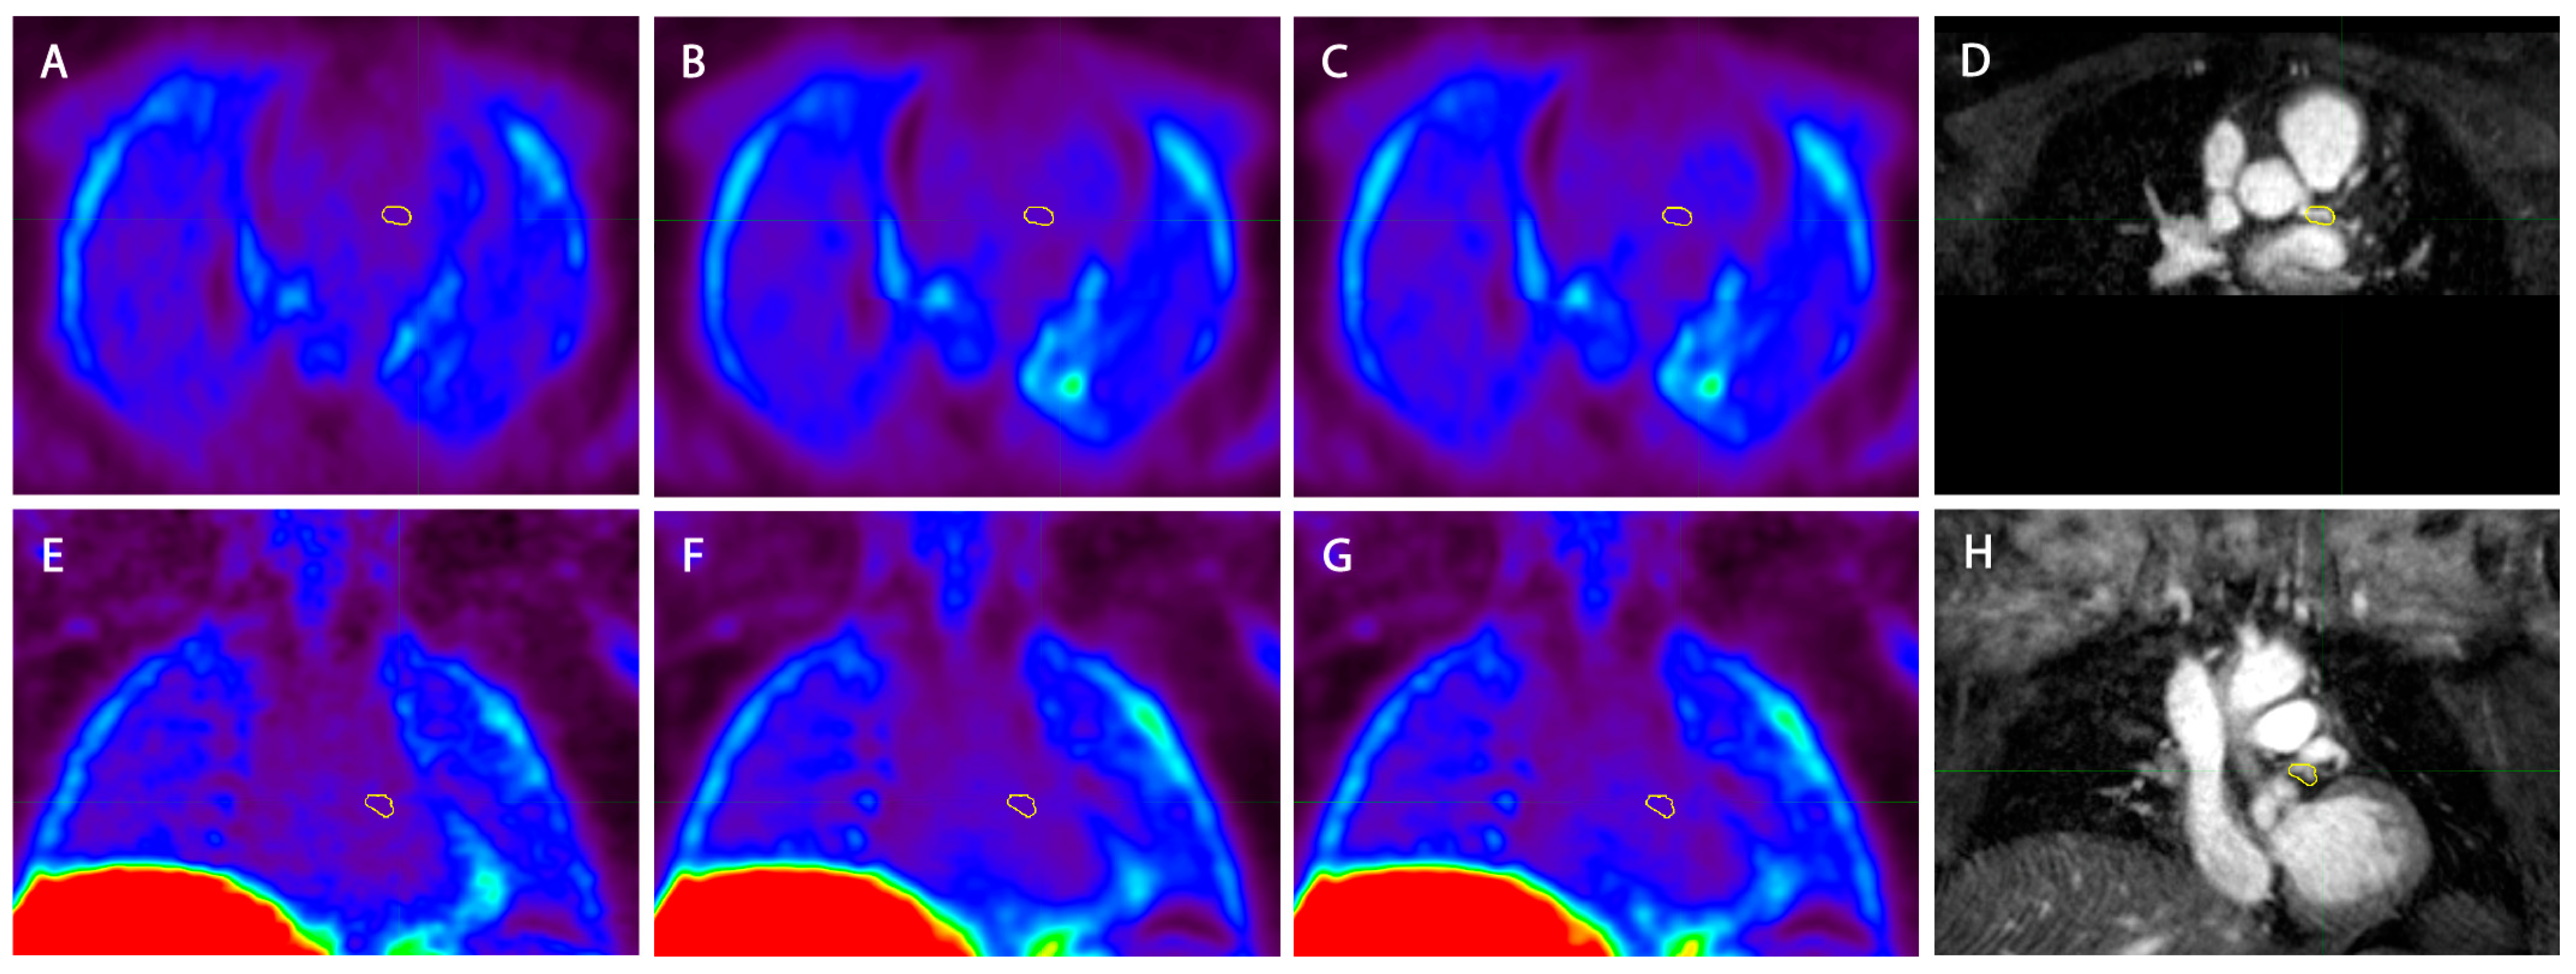

2.2. PET-MR Imaging

2.4. Image Reconstruction

2.5. Image Analysis